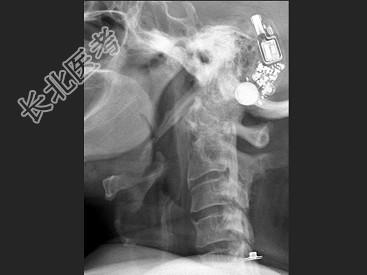

- 单项选择题女,58岁, 颈部疼痛,活动受限, 结合图像,最可能的诊断是 ( )

A、颈椎退行性变

B、颈椎结核

C、椎缘骨

D、椎间盘突出

E、局限性骨化性肌炎